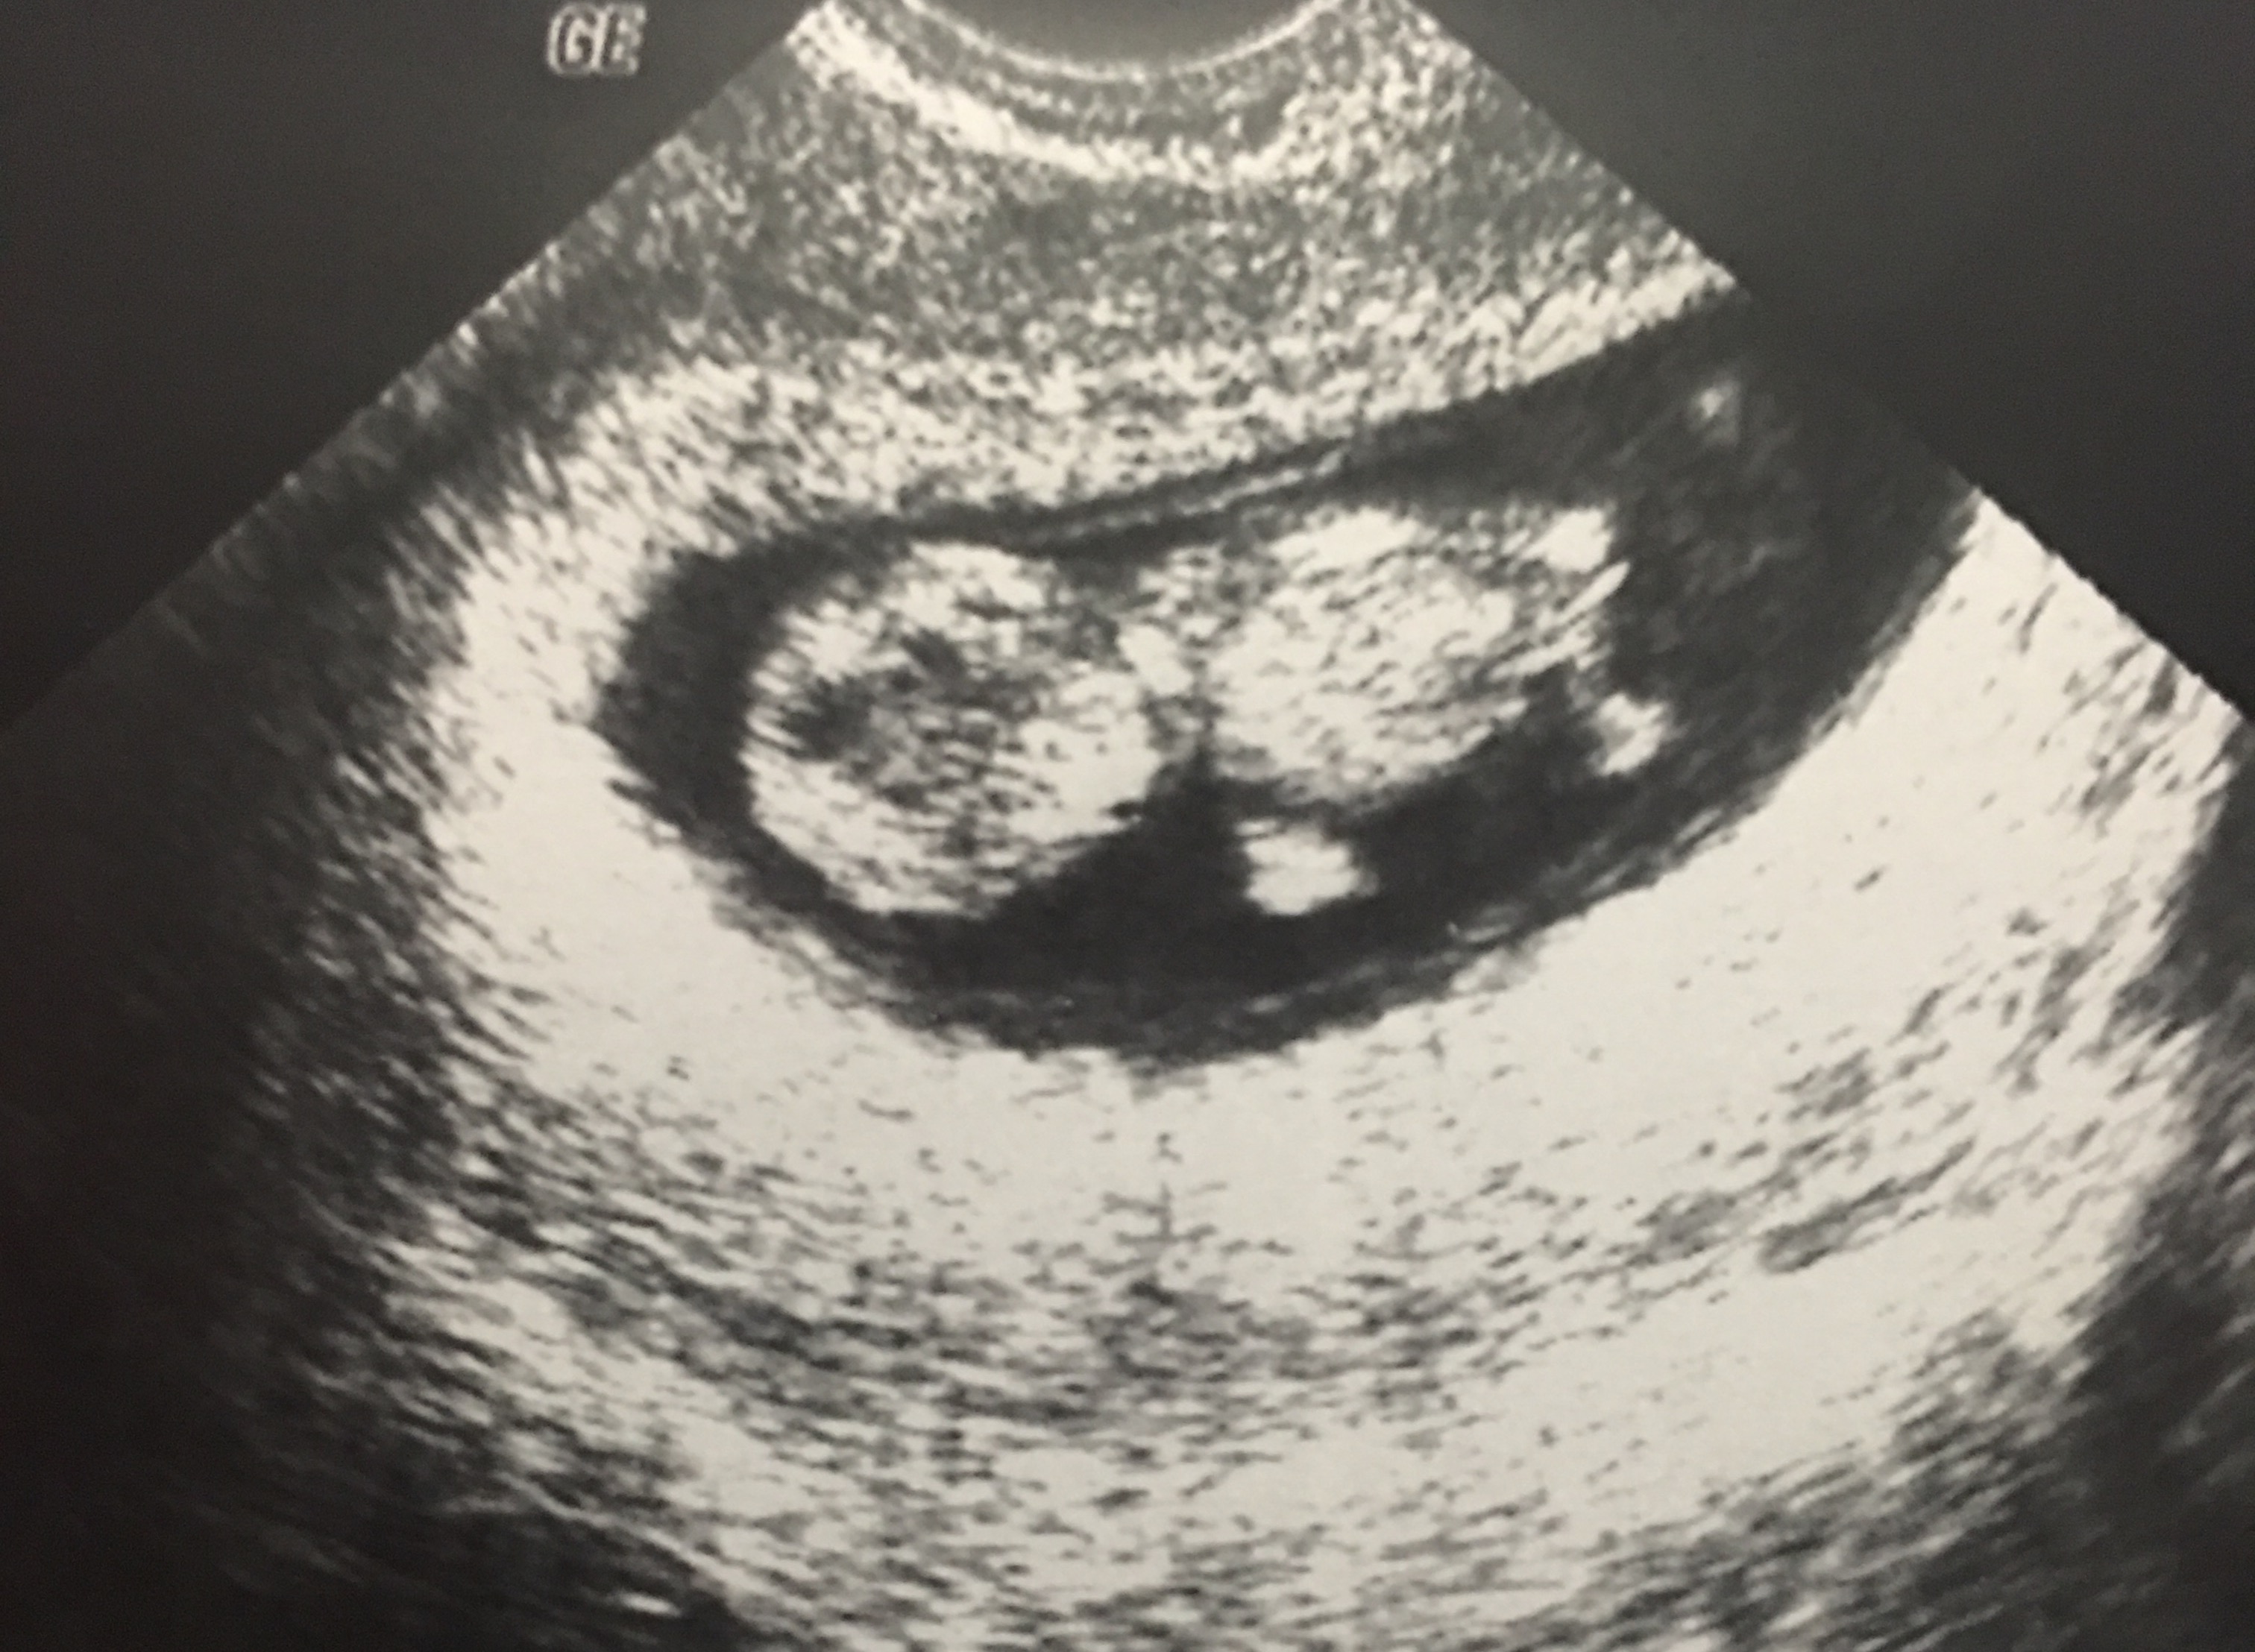

Any ramzy? Both are Vaginal u/s

Ramzi is completely debunked. No way to tell from these scans, sorry!